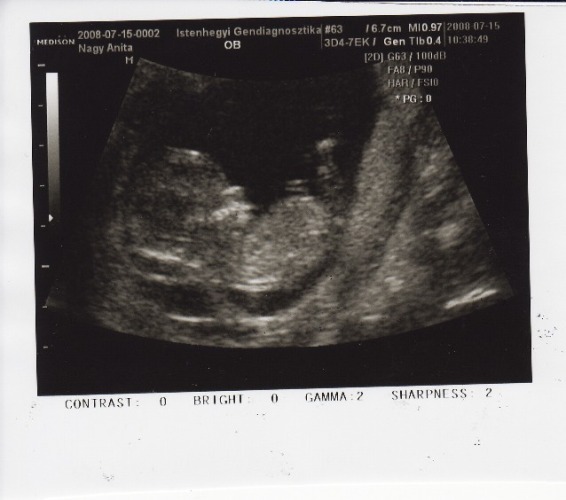

Voltam dokinál is, minden rendben volt, méhszáj zárt. UH-on szerintem most aludt a baba, mert nem nagyon mocorgott

képzeljétek, most kiscsajra tippelt, ugyhogy még mindig nem tudjuk, hogy mi lesz

és 15+6-ra mérte meg a gép, pedig 16+3-on voltam pénteken. Ugye nem számít 4 nap?